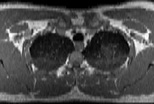

Visible Human male: Sectio transversalis 1336

NMR

Pd T1 T2